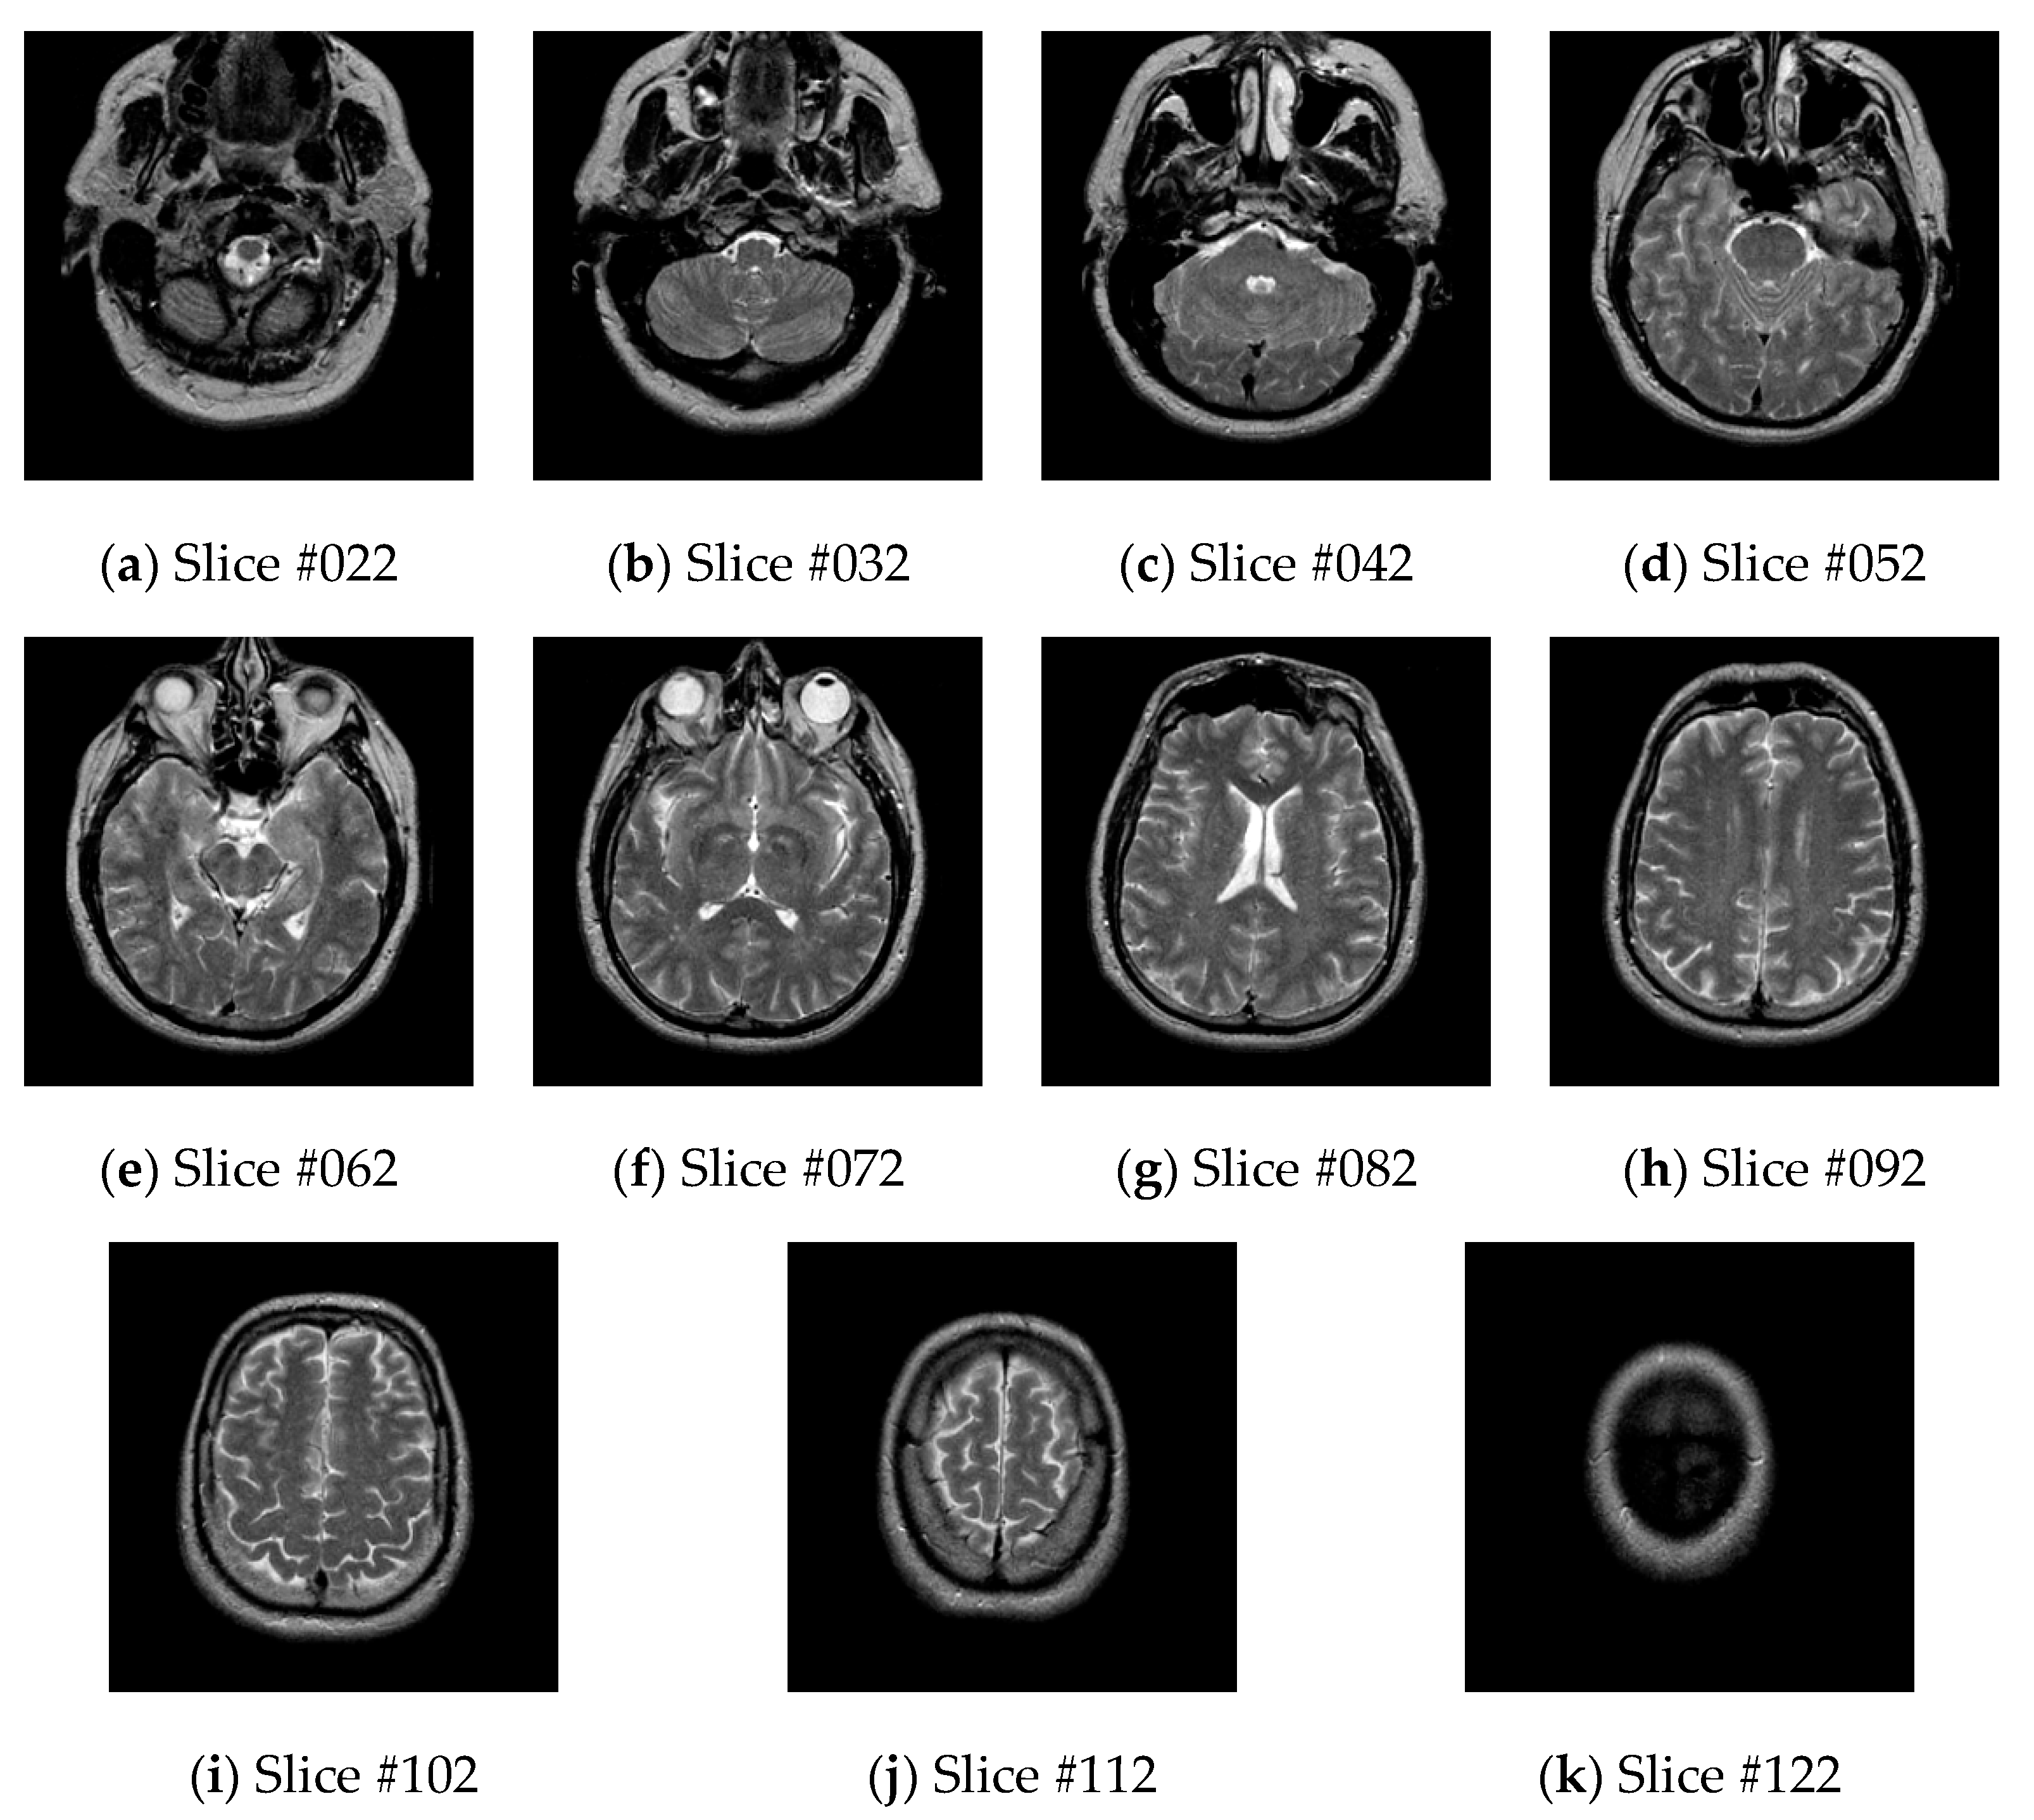

There are many kinds of medical image databases used for image segmentation. The Whole Brain Atlas (WBA) image database was used as the experimental database in this paper, which is currently the most widely used medical image segmentation database [24]. The brain medical image database is collected by Harvard Medical School, and the URL is http://www.med.harvard.edu/aanlib/home.html.

The WBA image database contains three different types of brain images: (1) transaxial images, (2) sagittal images, (3) coronal images. Each type of image contains five different modes of brain images: MR-T1 images, MR-T2 images, FDG-based PET images, PET-MR-T1 fusion images, and PET-MR-T2 fusion images. There are 126 MR-T2 brain transaxial images, and the slices #022, #032, #042, #052, #062, #072, #082, #092, #102, #112, and #122 are often used as a dataset for medical image segmentation [22], as shown in Figure 4.

Figure 4.

MR-T2 brain transaxial images.